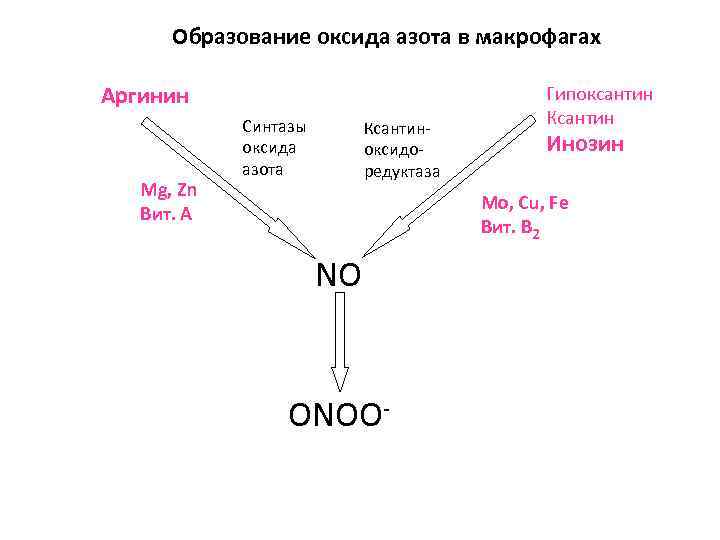

Ключевой эндогенный свободнорадикальный продукт, разрушающий гельминтов в организме млекопитающих, - пероксинитрит -!!! ONOO 13

ONOO-!!! NO ONOO 14

Исходным соединением для образования пероксинитрита служит оксид азота (NO) NO представляет собой универсальный внутриклеточный медиатор, играющий важную роль в: • регуляции сосудистого тонуса • регуляции функции тромбоцитов • прилипании лейкоцитов к клеткам-мишеням • регуляции размножения гладкомышечных клеток • передаче нервных импульсов • противоинфекционном иммунитете

Образование оксида азота в макрофагах Аргинин Mg, Zn Вит. А Синтазы оксида азота NO ONOO-

Образование оксида азота в макрофагах Аргинин Mg, Zn Вит. А Синтазы оксида азота Ксантиноксидоредуктаза Гипоксантин Ксантин Инозин Mo, Cu, Fe Вит. В 2 NO ONOO-

Активаторы ксантиноксидоредуктазы • Рибоксин (инозин) • Молибден • Медь • Железо • Рибофлавин-5 -фосфат 25